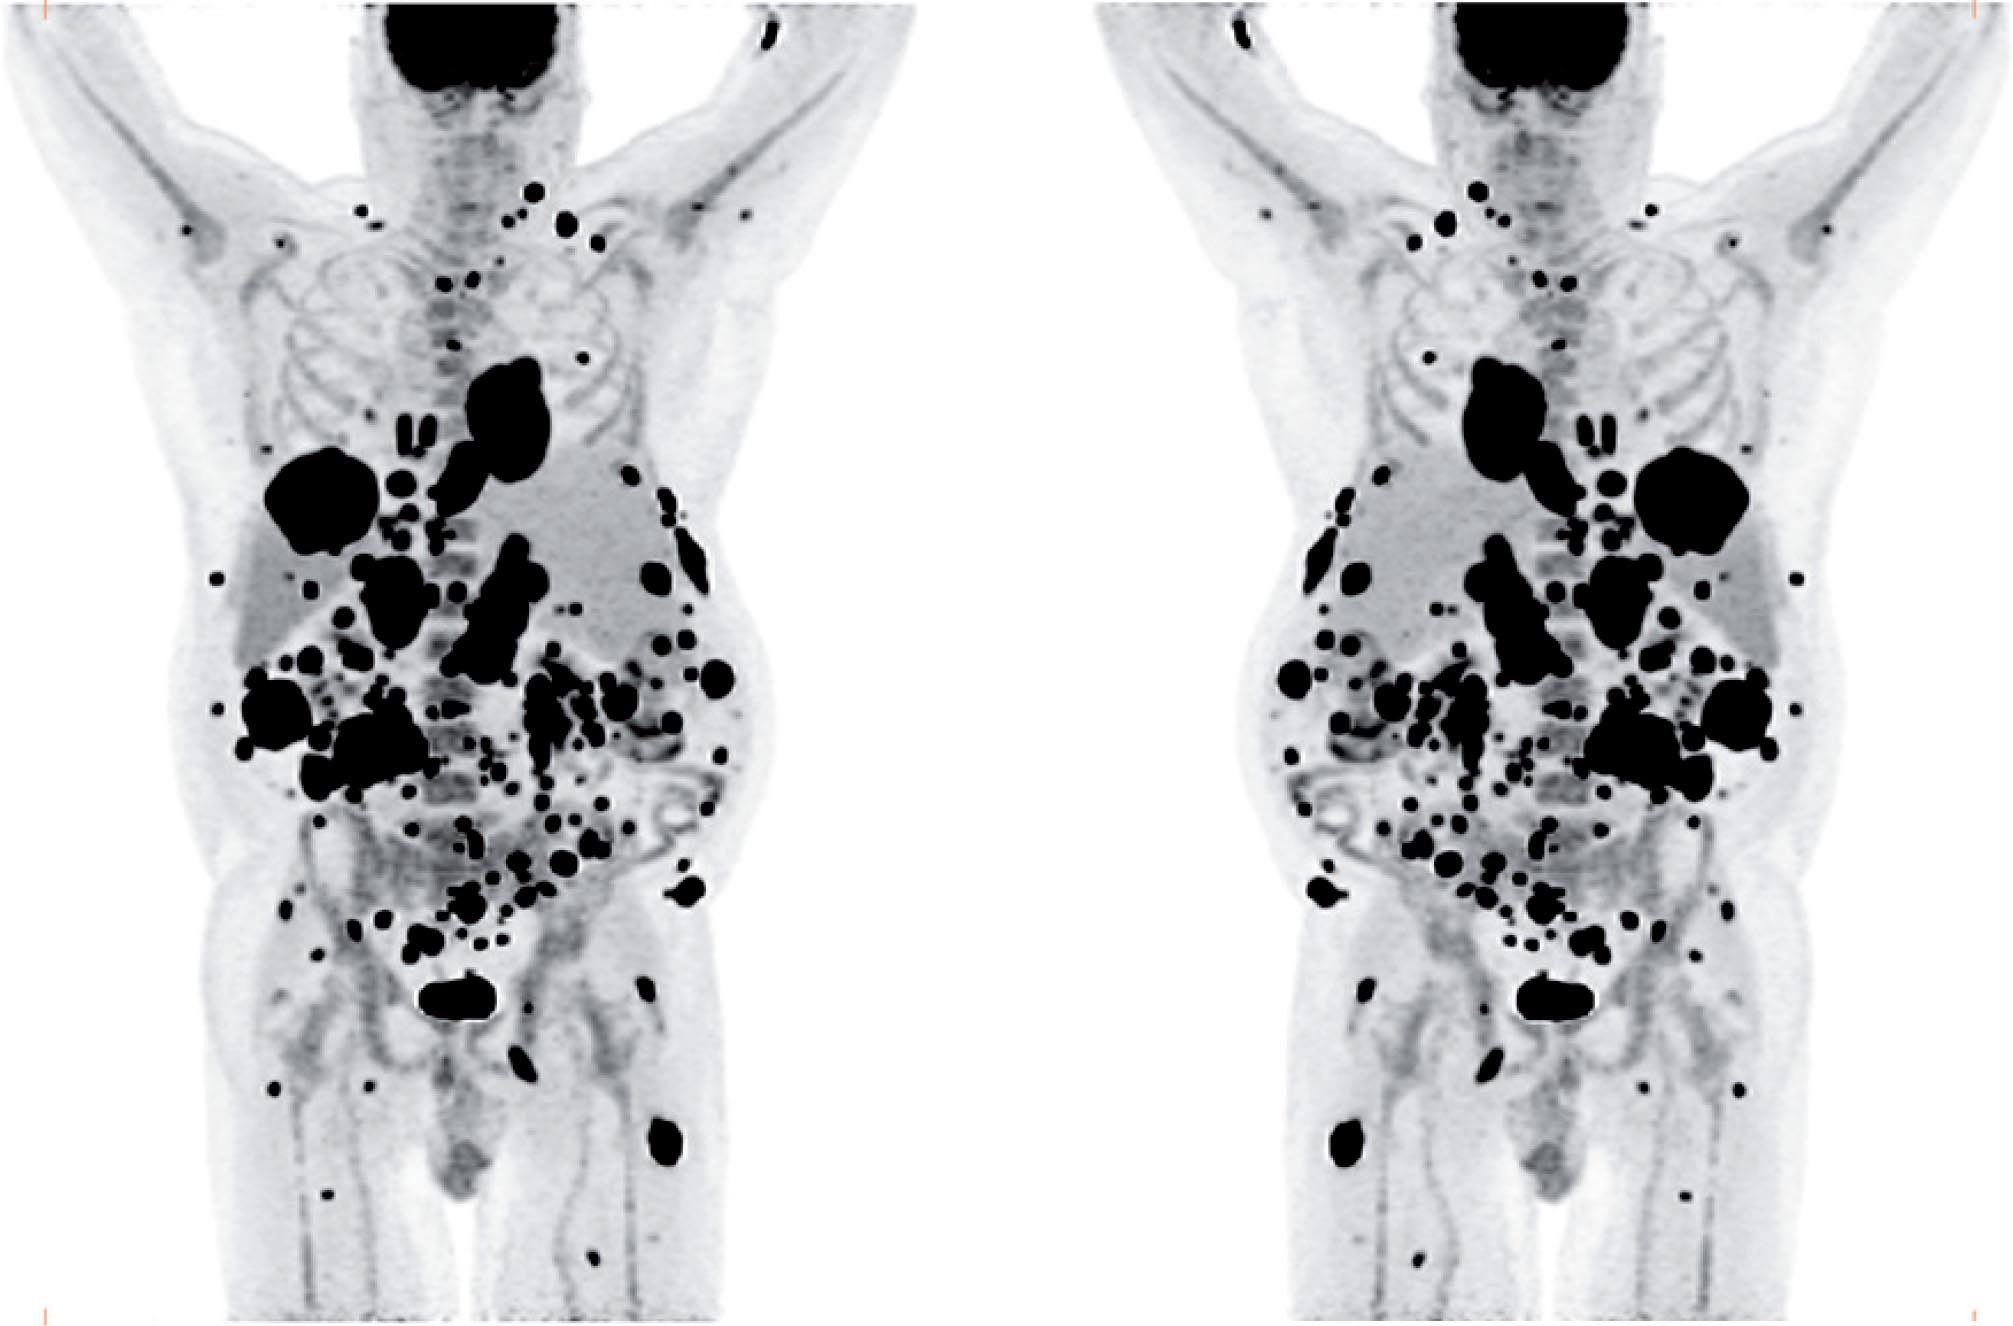

The patient was referred for 18F-FDG-PET/CT the next day to further evaluate the disease extent. A whole-body PET/CT was performed 60 min after the intravenous injection of 629 MBq (17 mCi) 18F-FDG. The study showed multiple hypermetabolic foci throughout the body (Figure 1). There was a large soft tissue mass in the right lower lobe with increased 18F-FDG uptake; the maximum standardized uptake value (SUVmax) of this lesion was 38.0. Also, there were multiple hypermetabolic nodules in the thyroid, gastric mucosa, pancreas, and both the adrenals. Both kidneys contained exophytic lesions with increased 18F-FDG uptake (Figure 2). A circumferential soft tissue mass in the esophagus was hypermetabolic as well. Additional FDG-avid nodules and masses were also found in the peritoneum and omentum; the largest of these had a SUVmax of 68.0. Intense FDG uptake was observed in multiple subcutaneous and intramuscular nodules throughout the body, some of which were thought to represent lymph nodes. Brain magnetic resonance imaging was performed on the same day, which revealed five metastatic lesions measuring up to 1.5 cm in the left frontal lobe, anterior right parietal lobe, and right temporal lobe. At this point, there were multiple candidate lesions for the primary malignancy, such as lung, esophagus, melanoma, or an aggressive lymphoma.

Figure 2. Axial 18F-FDG PET/CT fusion images. Foci of markedly increased 18F-FDG uptake are shown in the peritoneal cavity, and in exophytic lesions in the kidneys bilaterally.